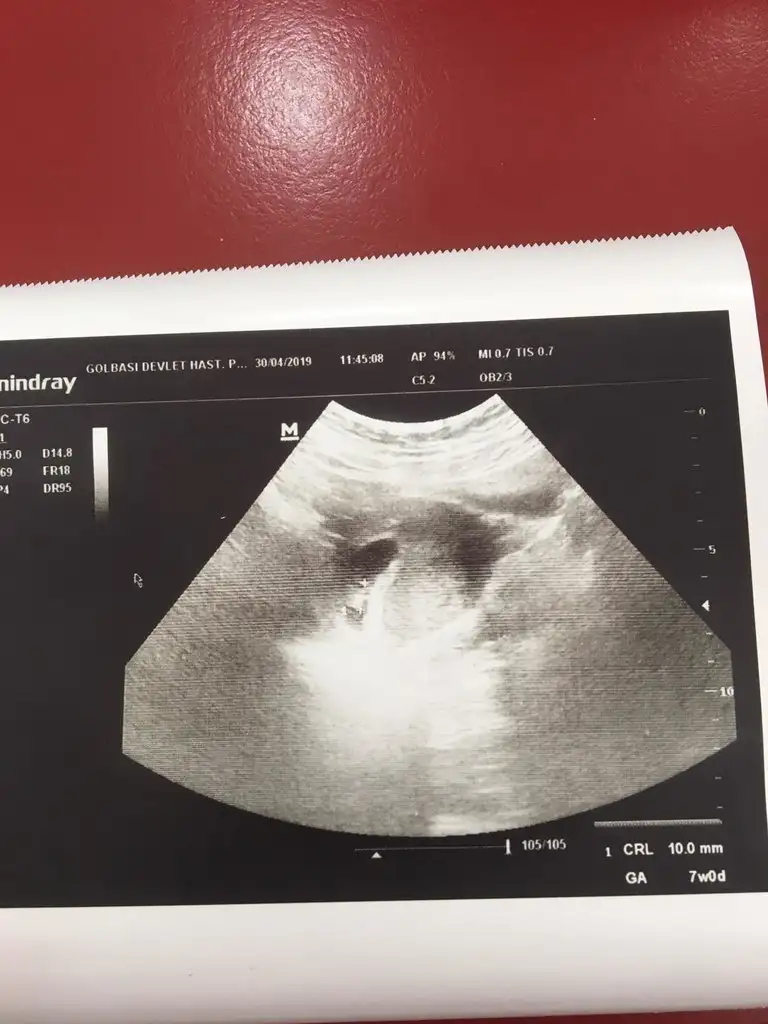

Birkaç mesaj öncesinde yazdım okur musunBu ne acaba![]()